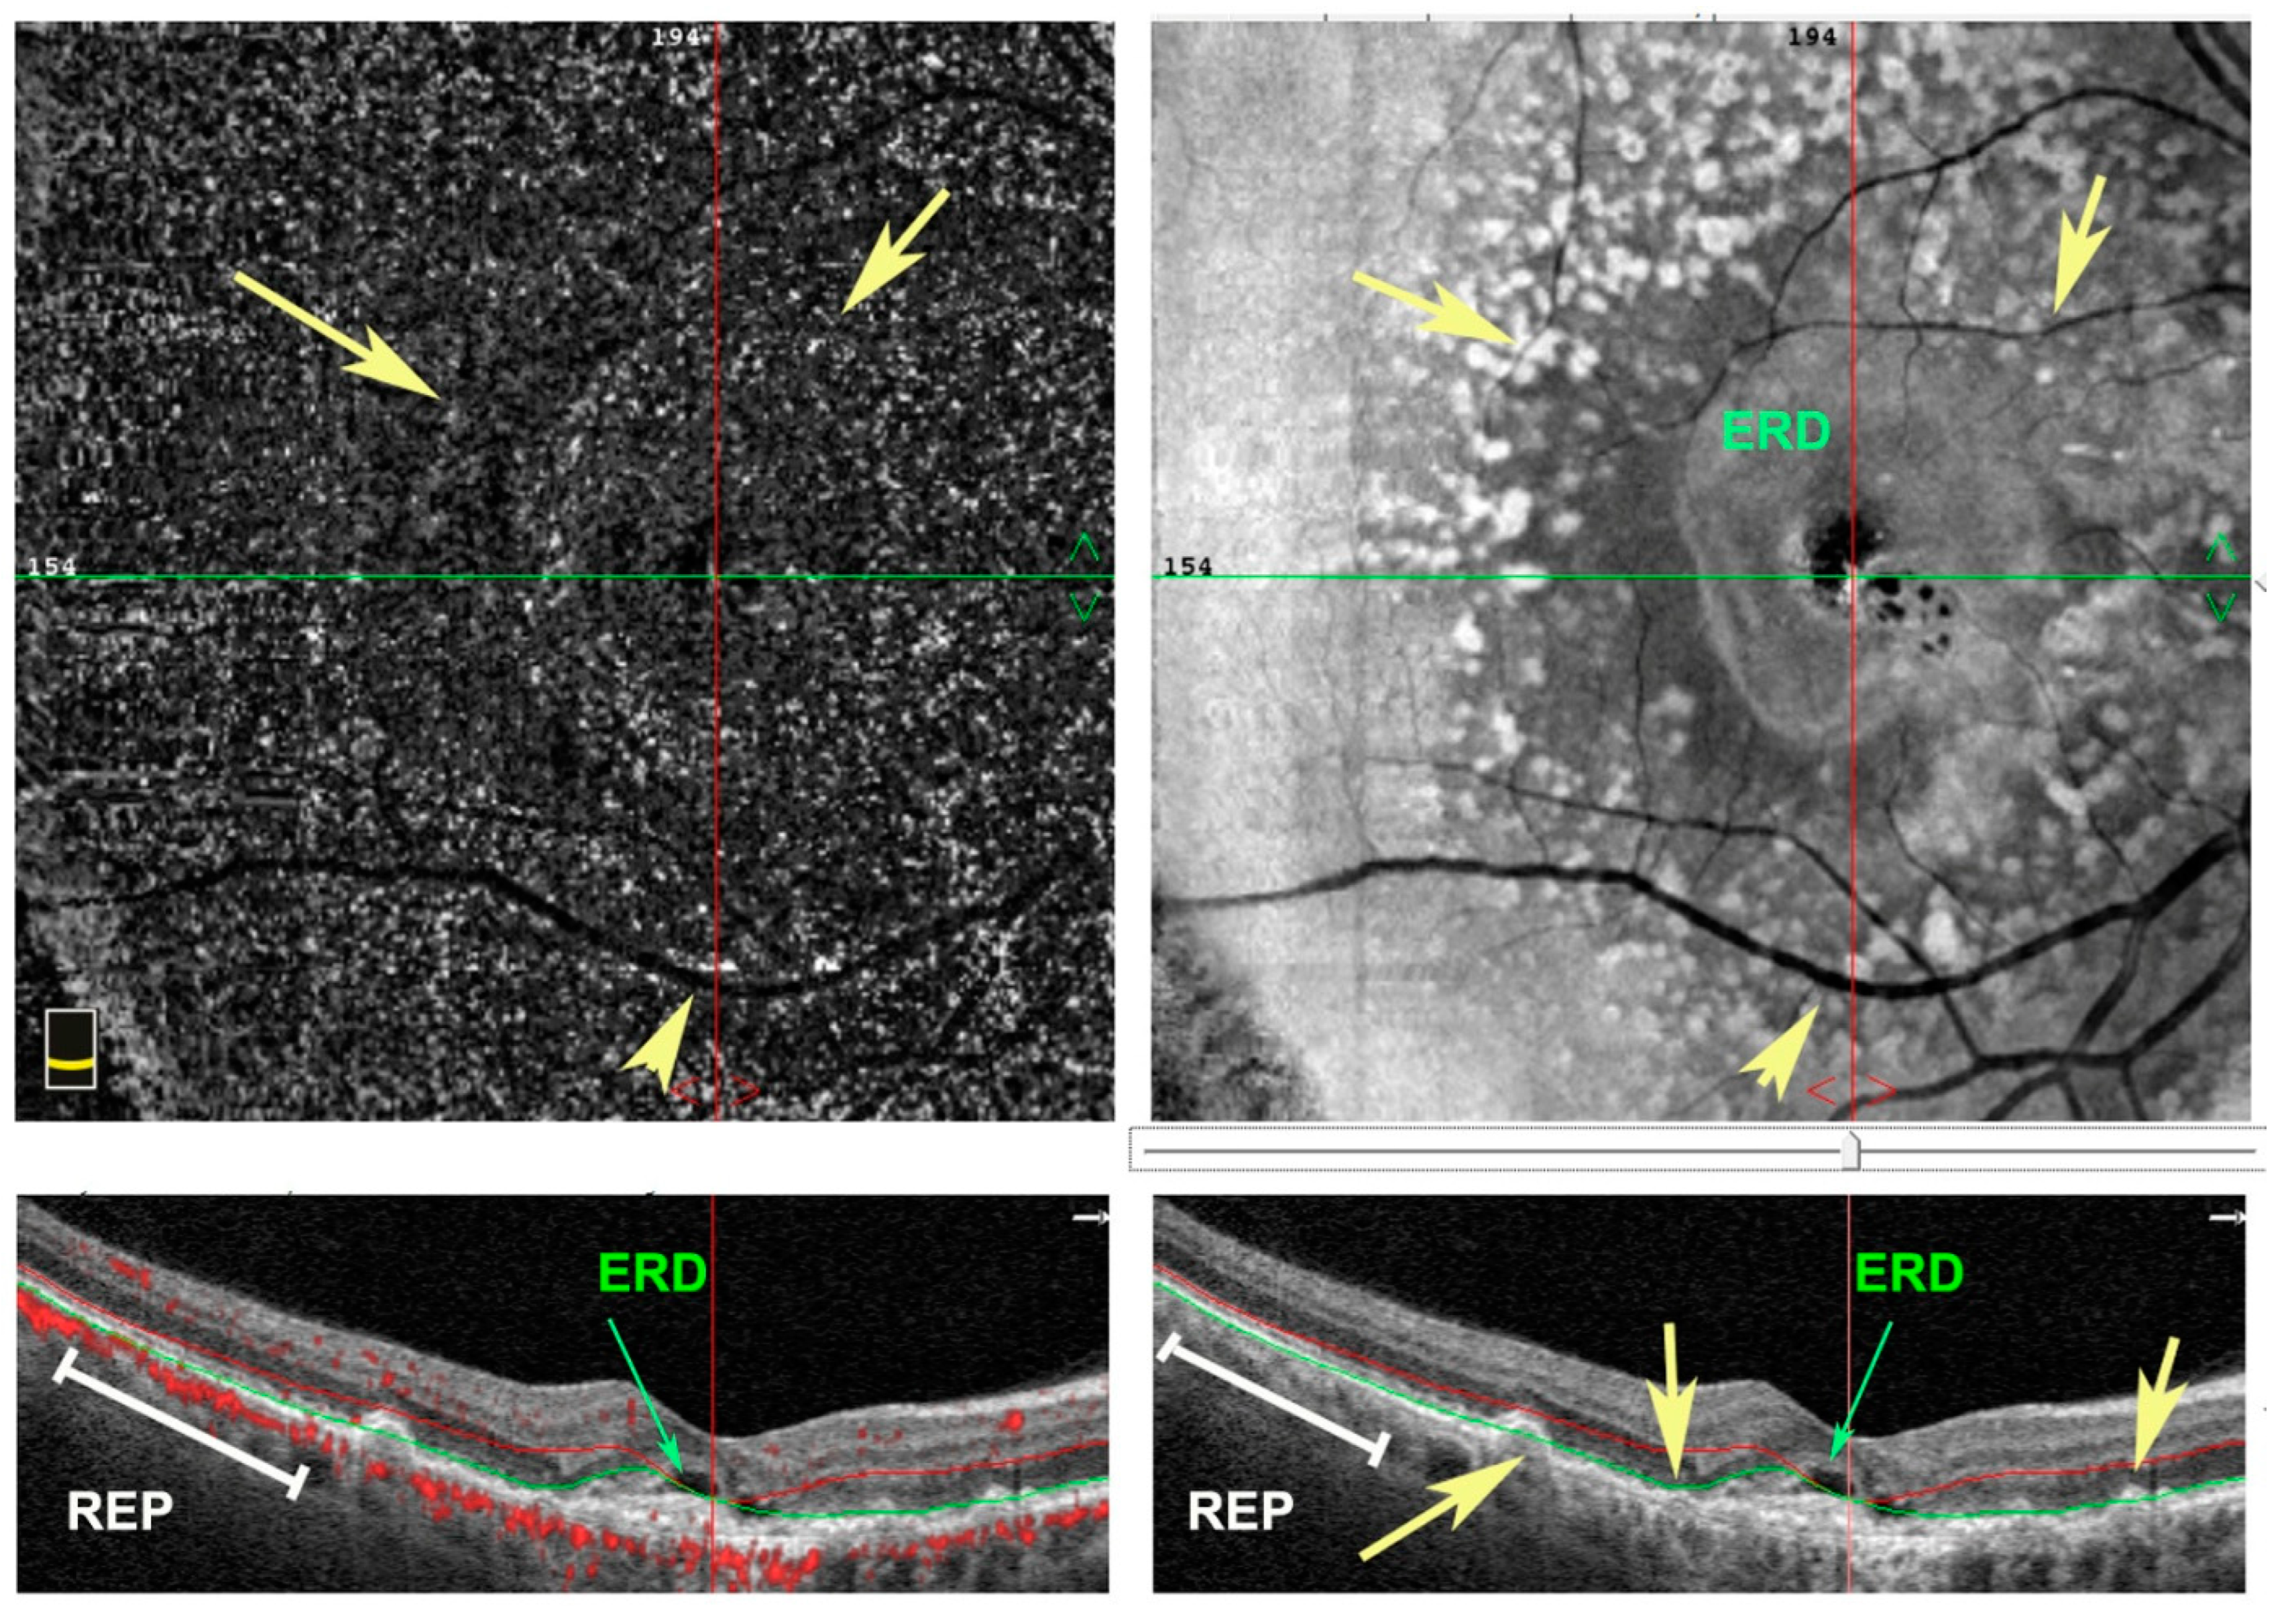

4.2. Diabetic Retinopathy (DR)